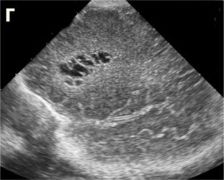

| Перивентрикулярный отек а, б, в, г - ребенок 2-х суток жизни с вдавленным переломом левой теменной кости. Структуры головного мозга симметричны. Сканирование во фронтальной и саггитальной плоскостях выявляет повышение эхогенности в перивентрикулярных областях без эхо-признаков других патологических изменений. При ДГ - невыраженное повышение показателей периферического сопротивления (спазм сосудов) д, е, ж - ребенок 1-х суток жизни от травматичных родов, парез Эрба слева, петехиальные кровоизлияния на лице, кровоизлияния в склеры, оценка по Apgar - 3-5 баллов. Определяется значительное повышение эхогенности в перивентрикулярной области, при ДГ - снижение показателей периферического сопротивления (парез сосудов). Перивентрикулярная лейкомаляция

|  |  | | а, б, в - фронтальные. |  |  | г, д - саггитальные сканы в разных плоскостях, В-режим. Определяются зоны перивентрикулярной лейкомаляции с обеих сторон. | Перивентрикулярное кровоизлияние в стадии псевдокисты